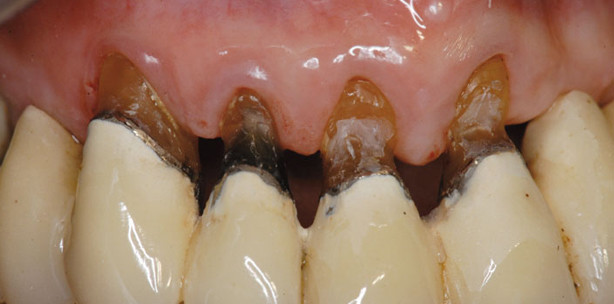

Bekanntermaßen kann es aber gar keinen Stillstand geben, weil der Patient lebt und seine Zähne im täglichen Leben benutzt! Zu allem Überfluß werden unsere Patienten, und auch wir Behandler, immer älter; das bedeutet, das Kauorgan ist funktionellen Belastungen und auch Pflegemaßnahmen immer länger ausgesetzt! Seit 1977 haben wir in unserer Praxis Patienten dokumentiert, vor allem komplexe und profunde PAR-Fälle. Im Rahmen meines Vortrages bei der Jahrestagung der Deutschen Gesellschaft für Parodontologie (DGParo) vom 20. - 21.9.2013 in Erfurt werde ich unterschiedliche Fälle zeigen (Fotos, Röntgenbilder, PAR-Staten), die alle nach den o. g. Prinzipien konsequent behandelt wurden. Es handelt sich ausnahmslos um profunde Fälle und Personen, die zu Beginn ca. 35 – 45 Jahre alt waren.

Wie sehen diese Patienten heute aus? Sondierungstiefen sind das eine. Aber horizontaler Knochenabbau als Alterungsprozess, „lange“ Zähne, Lockerungen aufgrund längerer Hebel, Zahnsubstanzverlust durch Pflegemaßnahmen u.s.w. sind das andere. Entwickeln sich alle Fälle gleich? Gibt es Trends, die voraussagbar sind? Wer seine Patienten über einen längeren Zeitraum betreut, muss manchmal Demut üben, mit Zweifeln an sich und der Wissenschaft fertig werden. Sind Langzeiterfolge planbar und voraussagbar? Was ist eigentlich ein Langzeiterfolg? Welche Bedeutung spielt die voraussichtliche „Restlebenszeit“ des Patienten für meine Therapieplanung? Bei welchem Attachmentverlust ist Parodontaltherapie vielleicht sinnlos? Sind Extraktion oder Implantatinsertion die bessere Therapie? Waren sie es auch noch 30 Jahre nach der Extraktion oder Implantation? Mit diesen Themen werden sich alle Behandler weltweit immer wieder